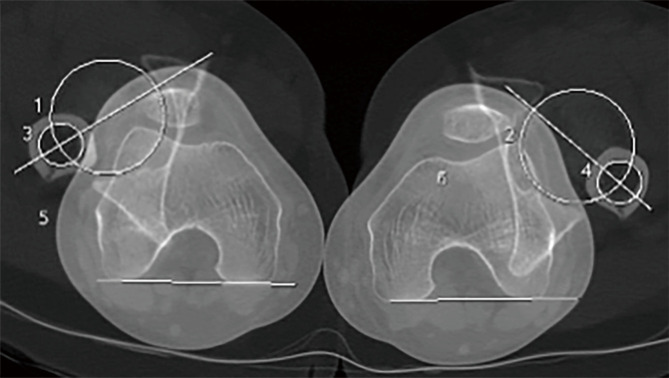

Key content and findings: Computed tomography (CT) is still considered the best method to measure both femoral and tibial torsional angles. Its main limitation, the radiation exposure, has been recently addressed with ultra-low dose protocols that were proven to be as accurate as standard protocols. On the other hand, magnetic resonance imaging (MRI) offers a nonionizing, radiation-free option that is now considered almost equivalent to CT. However, MRI consists in a long and expensive procedure that can be hindered by issues linked to metal implants, patient's positioning and measurement variabilities. Lastly, three-dimensional (3D) reconstructions derived from low-dose biplanar radiographies (LD-BRs) have been proposed as a low-radiating, quick and reliable solution to overcome the limitations of both MRI and CT scans.